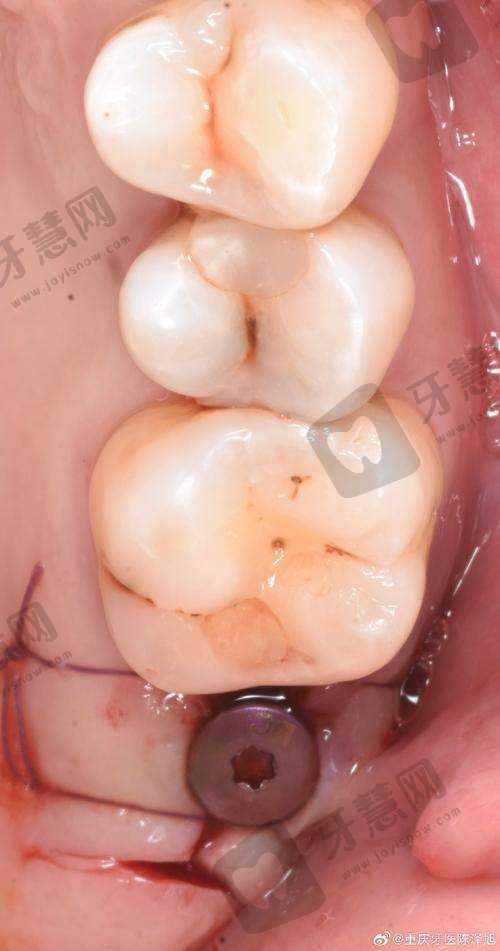

1. 数字化导航种植:门诊部开展数字化导航种植及后期维护,能更精细地进行牙齿种植,提高种植成功几率,减少患者痛苦。

1. 我牙齿缺失特别久了,一直想种牙又怕疼。来上海雅悦科特满口腔门诊部后,医生给我制定了详细的数字化导航种植方案。手术过程特别顺利,几乎没什么痛感。现在种牙已经过去一段时间了,牙齿使用起来特别正常,感觉和自己原来的牙齿一样,真的太满意了。